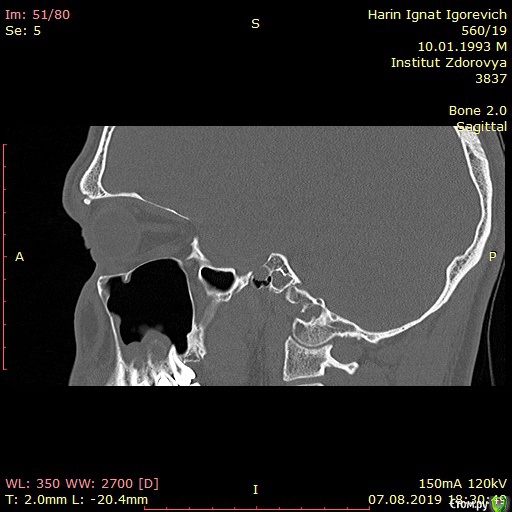

Игнат46 Опубликовано 9 декабря, 2019 Поделиться Опубликовано 9 декабря, 2019 Ищу клинику и специалиста для лечения кист.Сделал КТ пазух носа, и обнаружились кисты на корнях двух зубов. Ничего не беспокоило, прошел месяц, а сейчас уже второй день чувствую боль при нажатии на десну в этой области и некоторую опухлость . Ссылка на комментарий